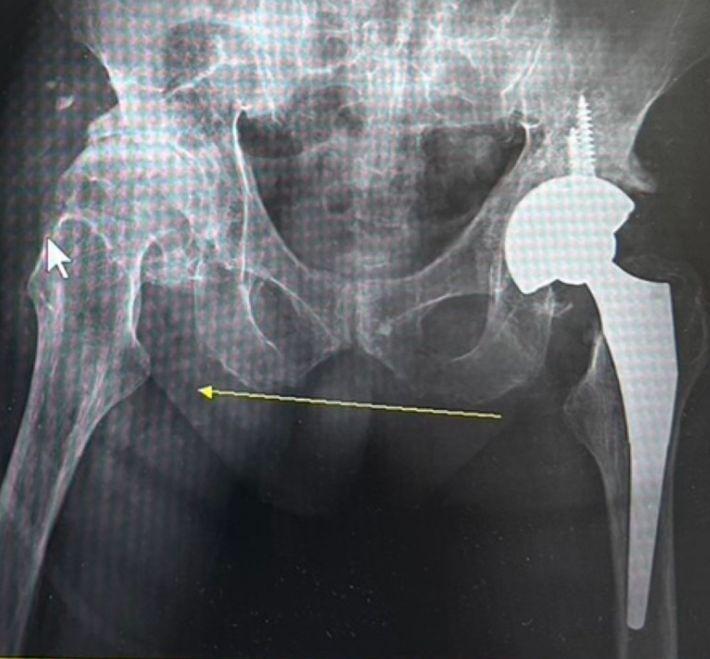

【告別髖關節退化】治療全攻略:新式微創髖關節置換手術以精準醫療解決鼠蹊部痛與長短腳困擾

鼠蹊部疼痛、走路跛行竟是髖關節退化?張建鈞醫師團隊詳解髖關節分級與膝蓋牽涉痛真相。本文解析創新「前外側微創髖關節置換術」,透過 6-8 公分小傷口且完整保留肌肉技術,實現術後 24 小時下床、免復健、低疼痛目標。結合 2025 最新文獻證實,高齡者透過精準醫療也能重獲行走自由。